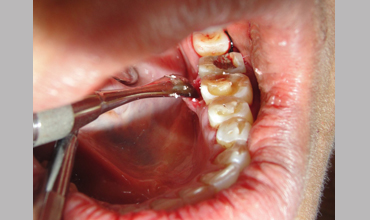

NON SURGICAL MANAGEMENT OF ENDODONTIC LESION AND SURGICAL MANAGEMENT OF PERIODONTIC LESION